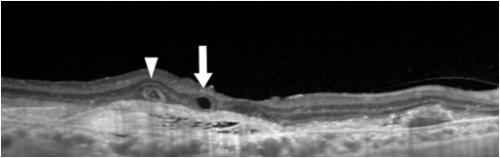

The macular hole on OCT shows partial or full thickness loss of retinal layers overlying the macular area, which may or may not be associated with a vitreomacular traction band.

Pseudohole:

The OCT scan of a pseudohole will reveal an epiretinal membrane with no loss of retinal layers. The foveal pit is narrow and vertical. The inner retina is thickened around the fovea. The perifoveal thickness may be increased. The term “pseudohole” reflects the fact that although this looks like a macular hole, it is not a hole in the retina.

On OCT, CNVM is characterized by subretinal and/or sub-RPE hyperreflective material, sub-RPE hyperreflective columns, RPE tear, or RPE rip. Histopathologically, CNVM (now called macular neovascularization or MNV)[28] has been classified into:

Type 1-CNVM appears beneath the RPE layer and appears as a fibrovascular or hemorrhagic pigment epithelial detachment.

Type 2-CNVM appears above the RPE layer.

Type 3-Neovascularization starts at the retina and progresses posteriorly into subretinal space; eventually, the neovascularization reaches the choroidal circulation and forms retinal-choroidal anastomosis. This is better known as retinal angiomatous proliferation (RAP).